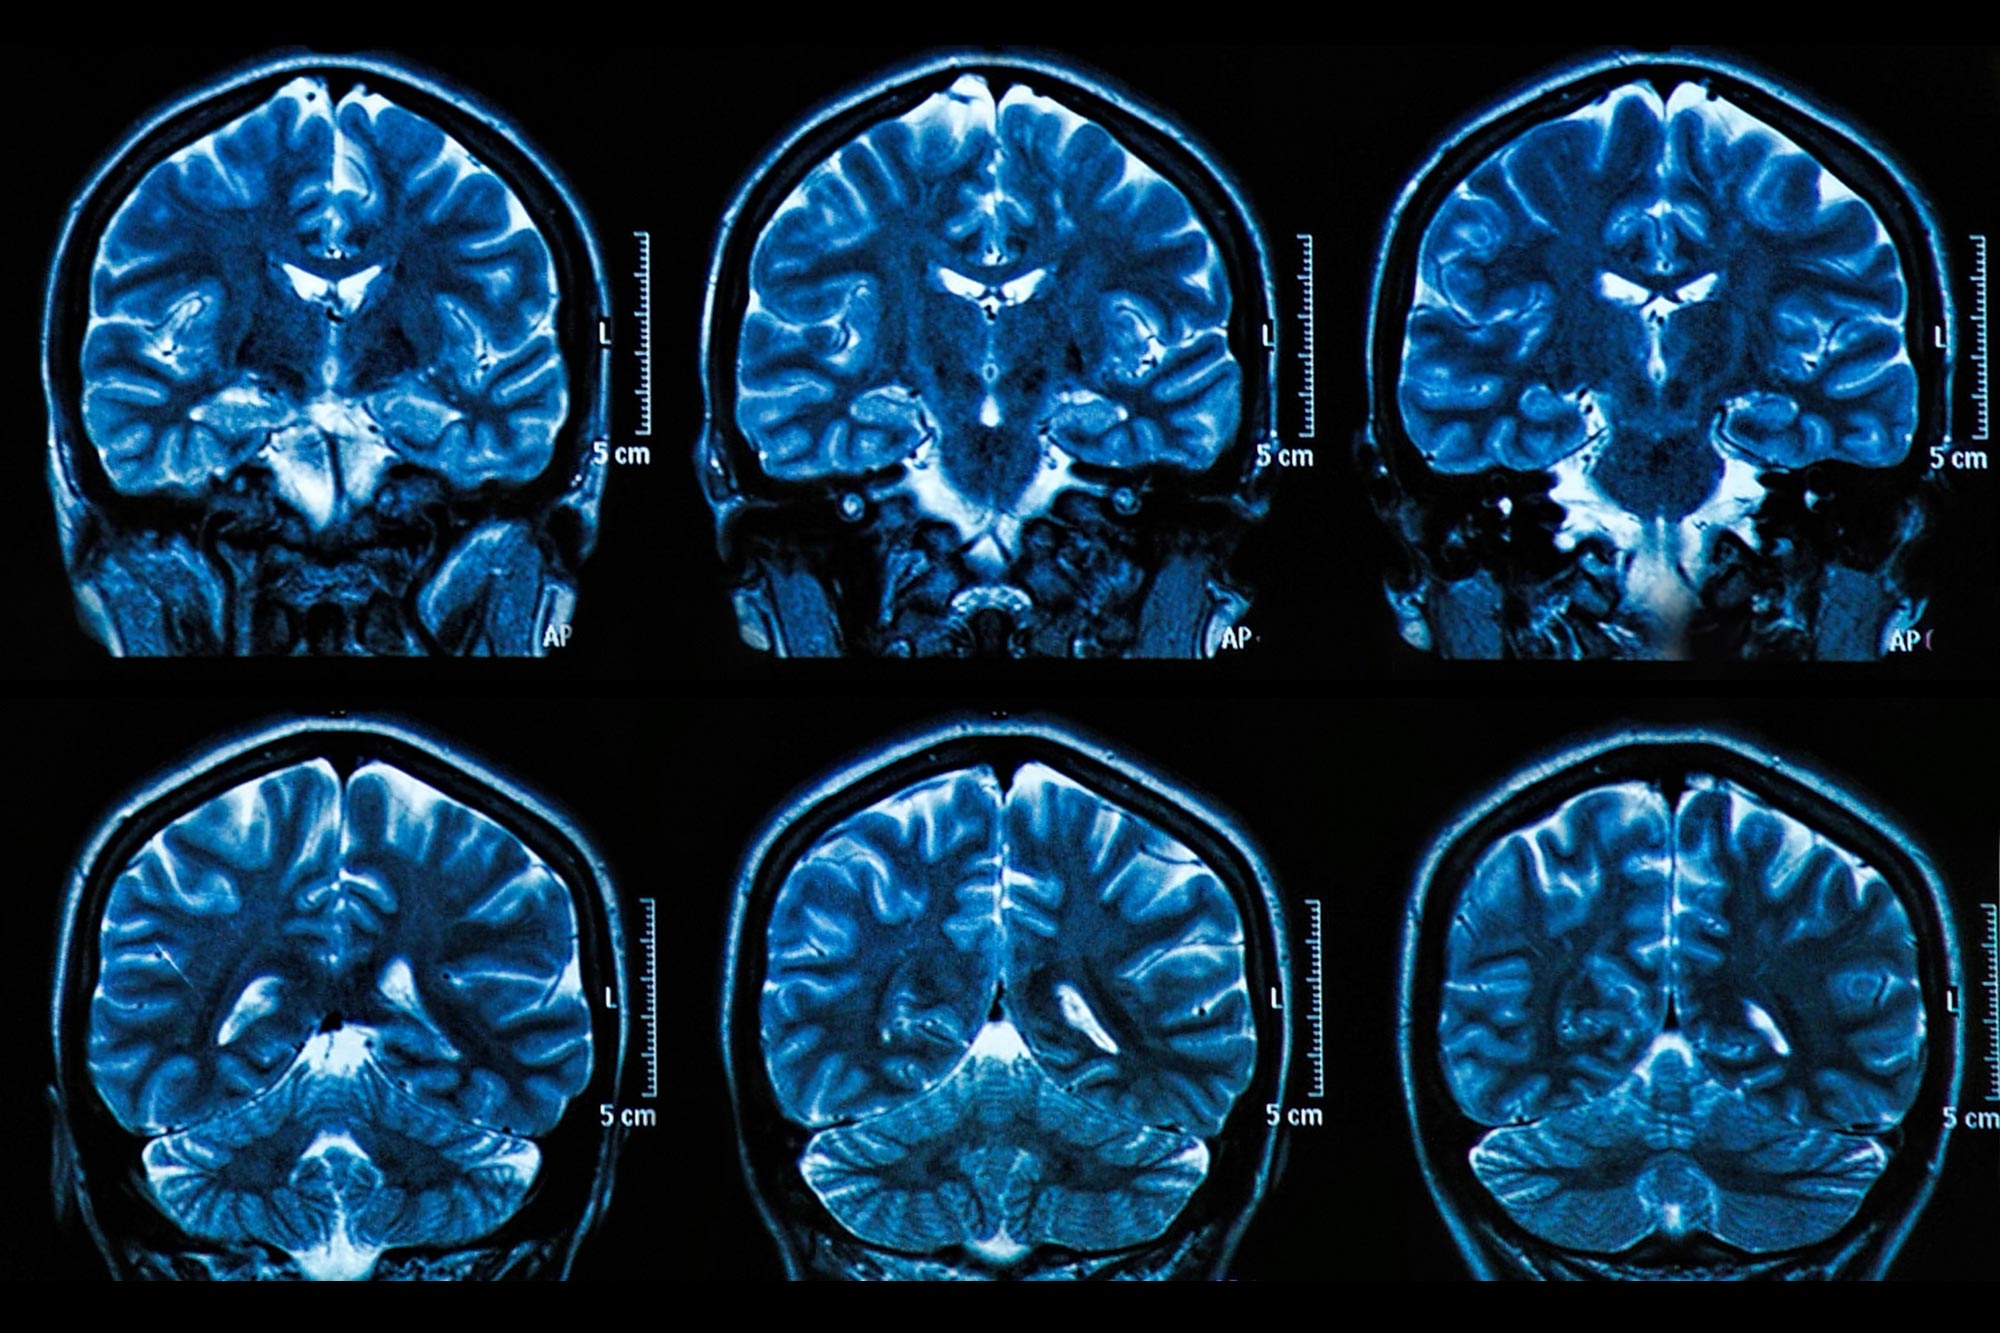

שימוש ב-MRI פונקציונלי (fMRI), החוקרים בחנו את דפוסי הפעילות המוחית של המשתתפים כשהם צפו בתמונות השייכות לקטגוריות רחבות של סצנות ואובייקטים פנוראמיים. חלק מהתמונות חזרו על עצמן, ובכך אפשרו מדידה של דפוסי הפעילות של המוח שנגרמו על ידי קטגוריות תמונות, כמו גם על ידי פריטי גירוי בודדים. המשתתפים כללו קבוצות של צעירים ומבוגרים בריאים – 24 גברים ונשים עם גיל ממוצע של 22 שנים, ו-24 עם גיל ממוצע של 69 שנים.